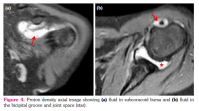

Also, MRI revealed significant joint effusion in 9/32 (28.1%) joints in six patients (Figure 4a, b). Eight of these nine joints had ≥1 JAMRIS component of MRI finding (Supplemental Table 1). Six of these nine joints had synovial hypertrophy (Grade I- 1 joint, and Grade II- 5 joints). Four joints each showed cartilage lesions and bone erosions, respectively. Bone marrow edema was seen in seven joints. It was also noted that six (66%) of the nine joints (4 patients) that had effusion did not fulfil the definition of clinical arthritis.